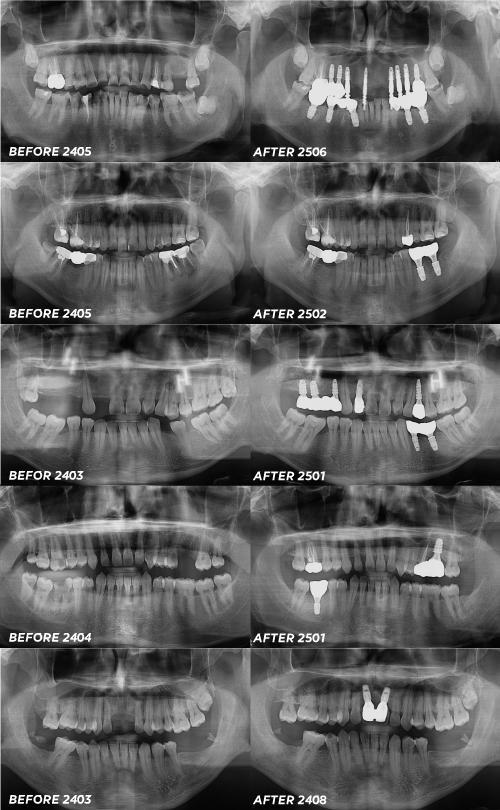

아래 실제 네오로 진행한 경우에요.